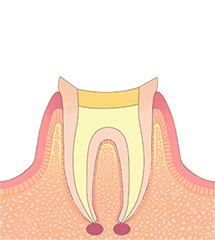

STEP04根管充填

根の中がきれいになり、炎症(痛みや違和感)がなくなったら、最終的な防腐剤を詰めます。詰めた後は、しっかりお薬が入ったかどうかを確認するために、レントゲン写真を撮影します。

お薬を空洞なく緊密に詰めることで、細菌の再繁殖を防ぎ、長く歯を健康に保ちやすくなります。 -